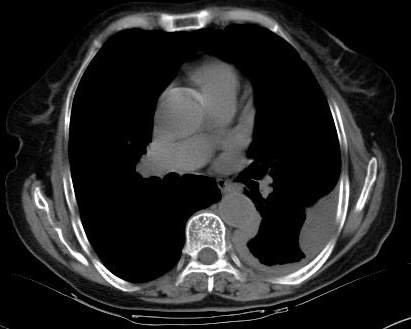

标题: CT0563:病历讨论,胸膜间皮瘤?

测ct值3-6hu,

既然ct值是3-6hu,还不如考虑包裹性积液。

请上传纵隔窗。目前还是支技包裹性积液(明显梭形),即使是间皮瘤并积液也少梭形的。

从图片看,包裹性积液好象更合理,梭形,ct值3-5hu(在哪看到的?);胸膜间皮瘤如此规则,不多见。

左侧背部胸膜肥厚,伴包裹性积液,不考虑间皮瘤.

同意以上各位的高见,首先考虑包裹性积液,1.胸膜间皮瘤积液量一般较大,以游离性积液更为常见,2.可以看到增厚的胸膜结节